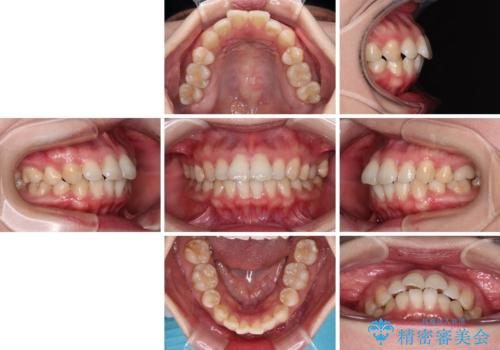

- 上下前歯の後戻りを気にして来院された患者様です。

インビザラインでの治療を希望されていて、デコボコの程度が中等度であり、安価なパッケージにて対応可能と判断されたため、インビザライン・モデレートを用いて矯正治療を行うこととしました。

インビザライン・モデレートは、製作できるアライナーの枚数に制限があるため、移動可能な量に限りがあるものの、インビザライン・ライトよりも枚数が多いため、幅広い症例に対応可能です。